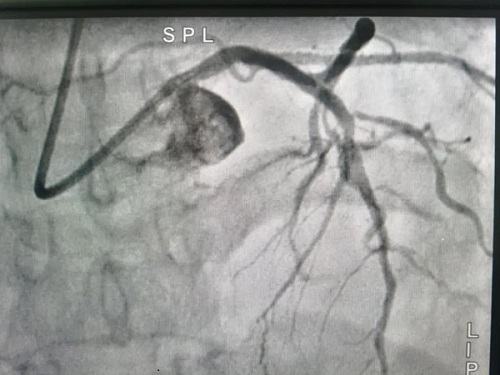

术中在前降支及高位钝缘支各植入支架1枚,正逆向尝试后开通右冠并植入支架3枚。

术后影像▼